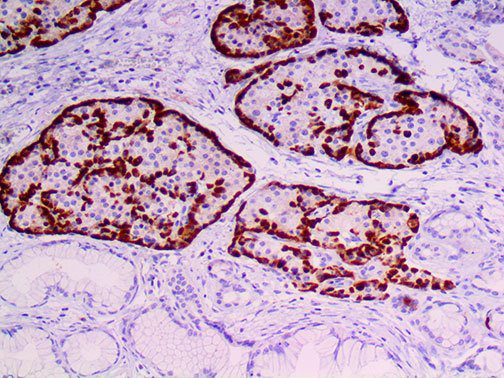

The first cytokines released are interleukin 1β (IL-1β) and tumor necrosis factor-α (TNF-α), which attract a variety of circulating white blood cells (WBCs) to the infection site, including neutrophils, monocytes, macrophages, and natural killer (NK) cells. This response, along with the antipathogenic chemicals released by these cells (i.e., complement), comprise the innate immune response. These cells directly attack the invading pathogen and also release additional cytokines, chief among them interleukin-1 and 6 (IL-6). IL-6 is essential for invoking the adaptive immune response, which calls T-cells, B-cells, and T helper (Th) cells to the infection site. IL-6 also stimulates further recruitment, proliferation and activation of macrophages.

It is the ICU physician who is most likely to witness one of the deadliest manifestations of the abnormal immunological response, the cytokine storm syndrome (CSS). This response is also referred to by some as the cytokine release syndrome (CRS). CSS is characterized by continuous activation and expansion of macrophage and lymphocyte populations, which secrete large amounts of cytokines, causing the cytokine storm. This massive cytokine release is akin to hemophagocytic lymphohistiocytosis (HLH) disease, a syndrome characterized by initial unchecked and persistent activation of cytotoxic T lymphocytes and NK cells.